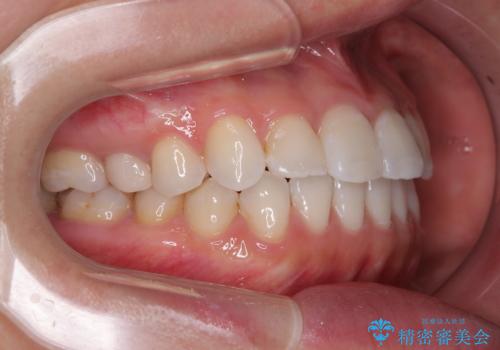

- 上下前歯のデコボコを気にして来院された患者様です。

ワイヤー矯正でもマウスピース矯正でも可能でしたが、短期間で、自身の手を煩わせることなく治療を行いたいとのことで、ワイヤー装置にて矯正治療を行うこととしました。

ご本人の中では2年近くかかるものと思っていたそうですが、1年で治療を終えることができ、大変満足していらっしゃいました。